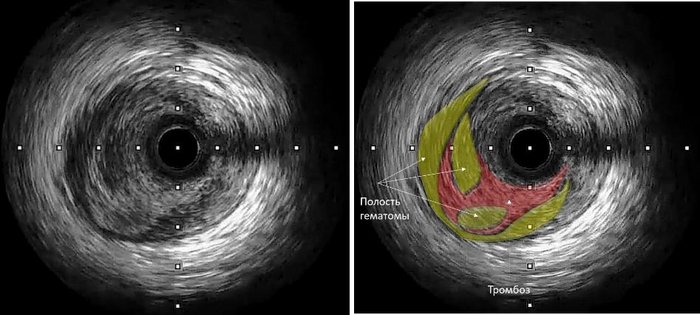

Итак мы имеем поражение двух основных сосудов из трех, питающих сердце. Для уточнения характера поражения, решено провести дополнительное обследование - внутрисосудистое УЗИ - заводится специальный датчик и путем его перемещения, смотрим что там происходит внутри (есть УЗИ наружное, тут УЗИ внутреннее в сосуде). Сделали протяжку на протяжении передней артерии:

Тут конечно не специалисту трудно разобрать, что и где, это просто иллюстрация, как это выглядит на экране (все можно с точностью до 0,1 мм измерить и оценить).

Для понимания вот что увидели:

Выявлена протяженная диссекция (надрыв сосуда) с образованием объемной интрамуральной гематомы, сдавливающей просвет сосуда до окклюзии (100% закупорка) + тромбоз в полостях гематомы.